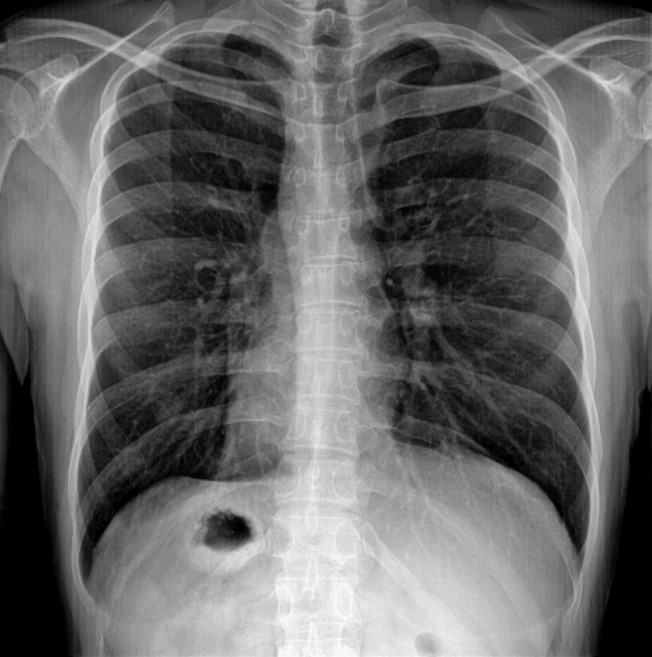

在X线成像过程中,X射线与人体组织相互作用,产生信号并转化为图像。然而,由于X射线的物理特性、成像设备的性能、以及患者体内组织结构的复杂性,导致在成像过程中不可避免地会产生噪声。这些噪声可能来自于X射线的散射、探测器的不均匀响应、图像处理算法的误差等。

为了降低X线照片噪声,采用了多种技术和方法。一方面,通过改进成像设备的硬件性能,如提高探测器的灵敏度、减少散射等,可以从源头上减少噪声的产生。通过优化图像处理算法,如滤波、增强等,可以在图像后处理阶段进一步降低噪声的影响。